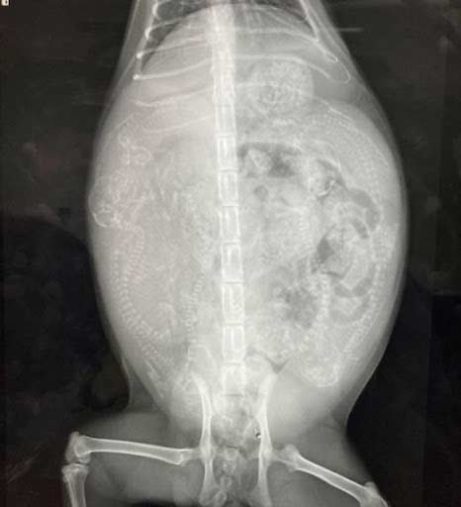

「お腹が膨れていることには保護時に気づいており、腹水が溜まる病気か妊娠のどちらかだろうと思っていました」

動物病院でレントゲンを撮ると、妊娠が判明。かねてから、自分の手が届く範囲に保護が必要な猫がいる時は絶対に助けると決めていた飼い主さんは、アメちゃんが妊婦猫であることを知っても動じませんでした。